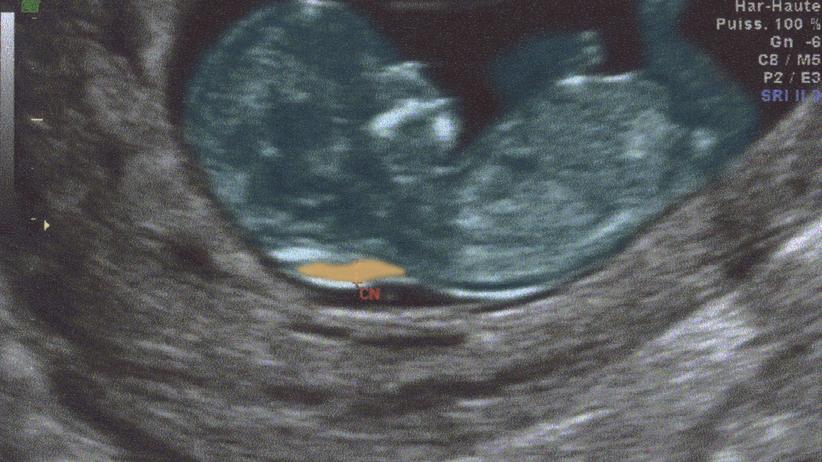

Nackentransparenzmessung ja oder nein. Dezember 2006 um 1341. Die Nackentransparenz Nackendichte des Babys entsteht durch eine Flüssigkeitsansammlung die im Ultraschall wie jede Flüssigkeit schwarz und damit transparent erscheint. 135 aber auch 11500 - oder irgendwo dazwischen liegen oder noch schlechter oder noch besser sein.

Auch Nackentransparenzmessung genannt ist eine nicht-invasive das heißt nicht in den Körper der Mutter eingreifende Methode der Pränataldiagnostik. Die Nackenfaltenmessung Nackentransparenzmessung NT-Messung ist eine Methode der Pränataldiagnostik und Bestandteil des Ersttrimesterscreenings. Danke an alle schon mal.

Schrieb am 08042013 1140 Registriert seit 300810 Beiträge. Tripple Test - ja oder nein. Trotz vieler überlegungen sind wir uns nicht sicher ob wir die nackentransparenzmessung machen sollen. Du bekommst nur eine berechnung keine endgültige diagnose. Nackentransparenzmessung ja oder nein. Ob ihr es habt machen lassen. Die Nackenfaltenmessung Nackentransparenzmessung NT-Messung ist eine Methode der Pränataldiagnostik und Bestandteil des Ersttrimesterscreenings.